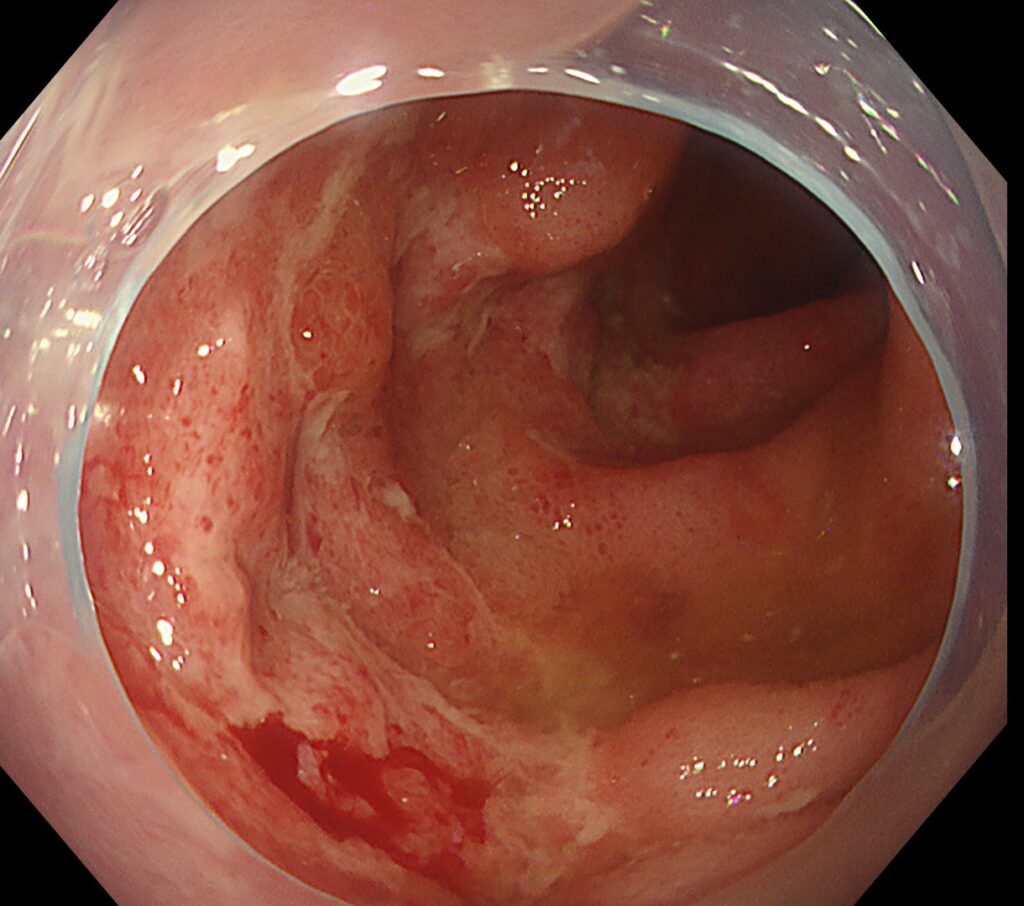

回腸末端に縦走する多発潰瘍を認めます。

加えて、上行結腸はびまん性に斑状発赤を認めます。

本症例は、卵かけごはんが原因と考えられました。